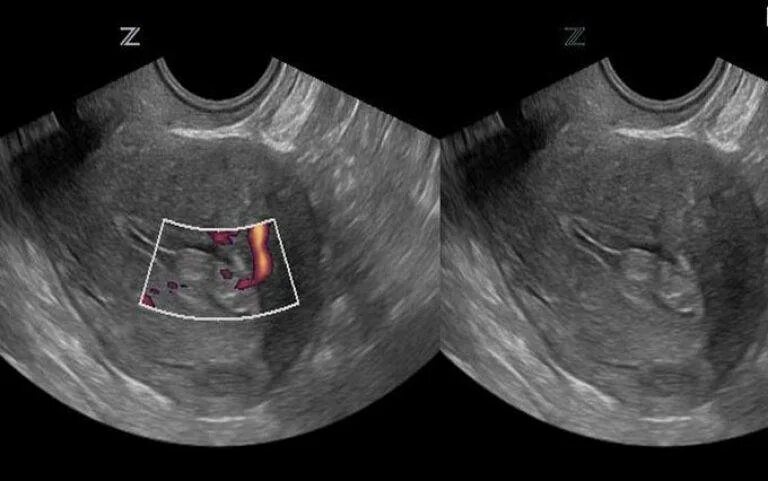

Как выглядят 2 матки